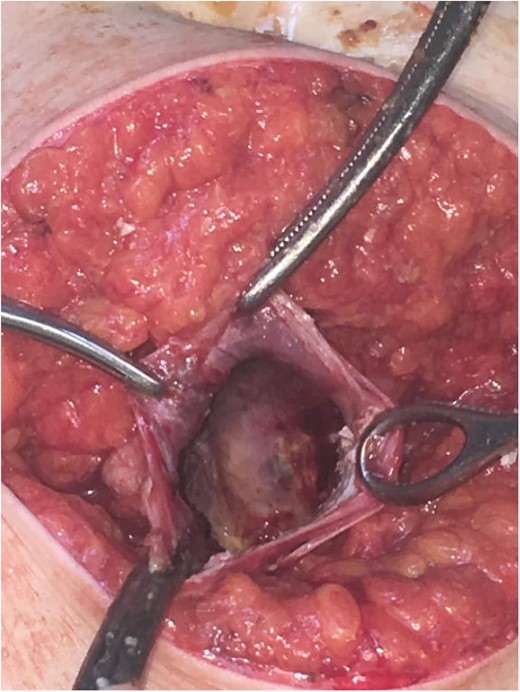

Subsequently, surgical exploration was performed. A preperitoneal sizable cyst was revealed, which developed in the abdominal wall without the involvement of any abdominal viscera or wall peritoneum. The macroscopic appearance of its content suggested that the mass was indeed a hydatid cyst (Figs 4 and 5). Incision upon the cyst wall and evacuation of its content were performed, without spilling of the content. Hypertonic solution of sodium chloride (NaCl 15%) was then injected in the remaining cavity, followed by the placement of a Pezzer catheter.

Total cyst drainage without spillage. Subsequent Pezzer tube placement through incision site.